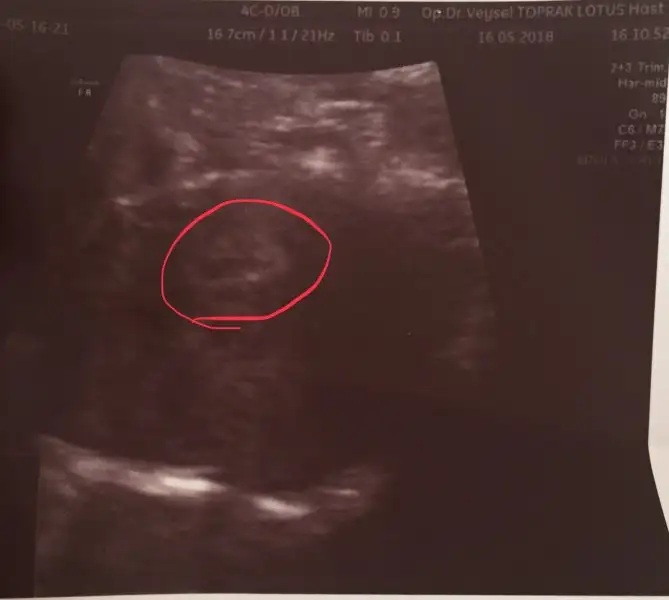

Ayy canim benim bende 25 mayista gidiyorum hakkimizda hayirlisi allah sag saglim kucagimiza almayi nasip etsin hepimize su mubarek gunde dualarimiz eksik olmasin senin adina cok sevindim bnde bugun gordum bebisimiEki Görüntüle 2147019 Kızlar kesemiz bu kırmızı halkanın içinde. Karından baktı vajinadan bakmadı. Çok şükür gördük. 25 Mayıs’a da çağırdı kalp atışı için. Allah herkese nasip etsin inşşşşş